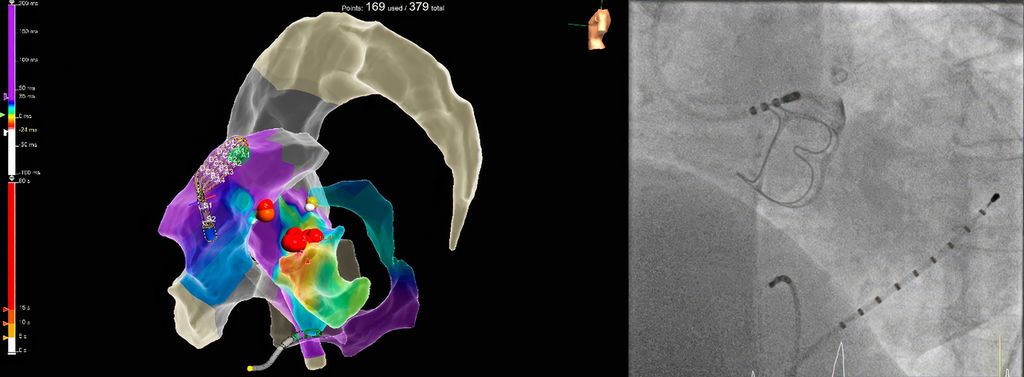

Der große Vorteil von Punkt-für-Punkt-Ablationsverfahren mittels Hochfrequenzstrom ist die Möglichkeit, auch komplexe atriale Rhythmusstörungen abseits der Pulmonalvenenisolation – wie z.B. atypisches rechts- oder linksatriales Vorhofflattern nach vorangegangenen Ablationen oder Herzoperationen – behandeln zu können. Hierbei kommen 3D-Mapping-Systeme sowie hochauflösende multipolare Mappingkatheter zum Einsatz, welche es ermöglichen, innerhalb weniger Minuten zehntausende Mappingpunkte zu erfassen und somit eine extrem akkurate Diagnostik und Therapie der Rhythmusstörung zu gewährleisten (Abb. 1).

Abb. 1: Hochauflösendes 3D-Map des rechten Vorhofs mit farbcodierter Visualisierung der atrialen Tachykardie und Darstellung der undichten Stelle (rosa Punkte) im Bereich der vorbestehenden Ablationsläsion (weiße Linie). Erfolgreiche Ablation an der mittels Map genau definierten Stelle anhand eines Contact-Force-Katheters (14 Gramm Anpressdruck)